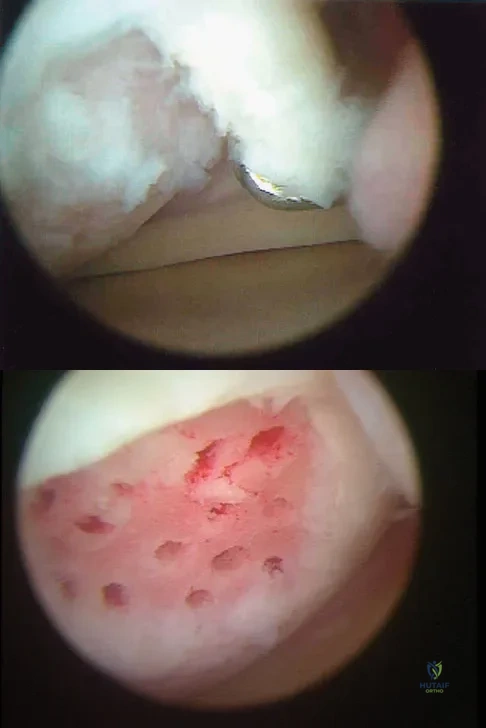

A 30-year-old patient reports chronic medial knee pain and swelling. Figure 9a shows an articular cartilage lesion observed during arthroscopy. The surgeon decides to treat the lesion with the microfracture technique seen in Figure 9b. A biopsy of the repaired tissue 1 year after treatment is likely to show which of the following findings?

Explanation